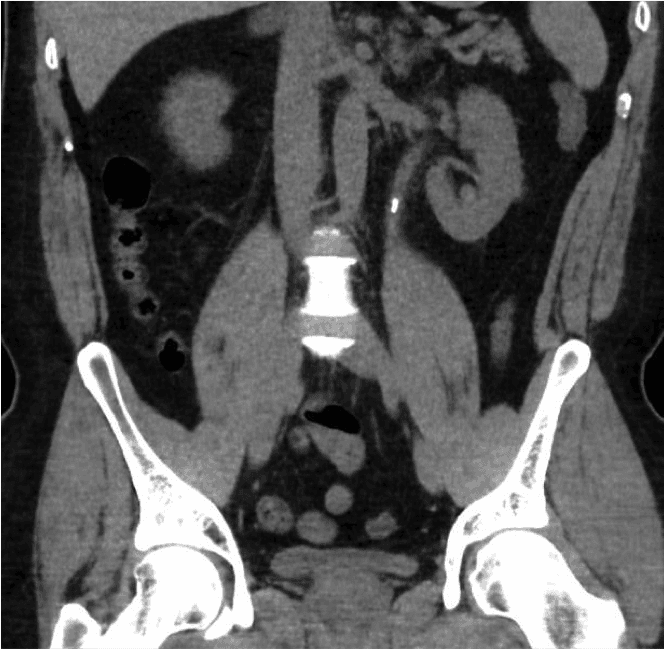

La calcolosi renale è una delle patologie più diffuse dell'era moderna. La prevalenza varia notevolmente tra le diverse aree geografiche, oscillando tra l'8% e il 19% negli uomini e tra il 3% e il 5% nelle donne nei paesi occidentali [1,2]. Il numero di ricoveri ospedalieri dovuti a calcoli renali nel Regno Unito è aumentato del 63%, raggiungendo quota 83.050, dal 2000 al 2010 [3]. La crescente prevalenza della calcolosi renale rappresenta un notevole onere economico e clinico per il nostro sistema sanitario.I calcoli renali possono presentarsi incidentalmente durante una scansione eseguita per altri motivi o manifestarsi con sintomi quali dolore, infezione delle urine o ematuria (sangue nelle urine).